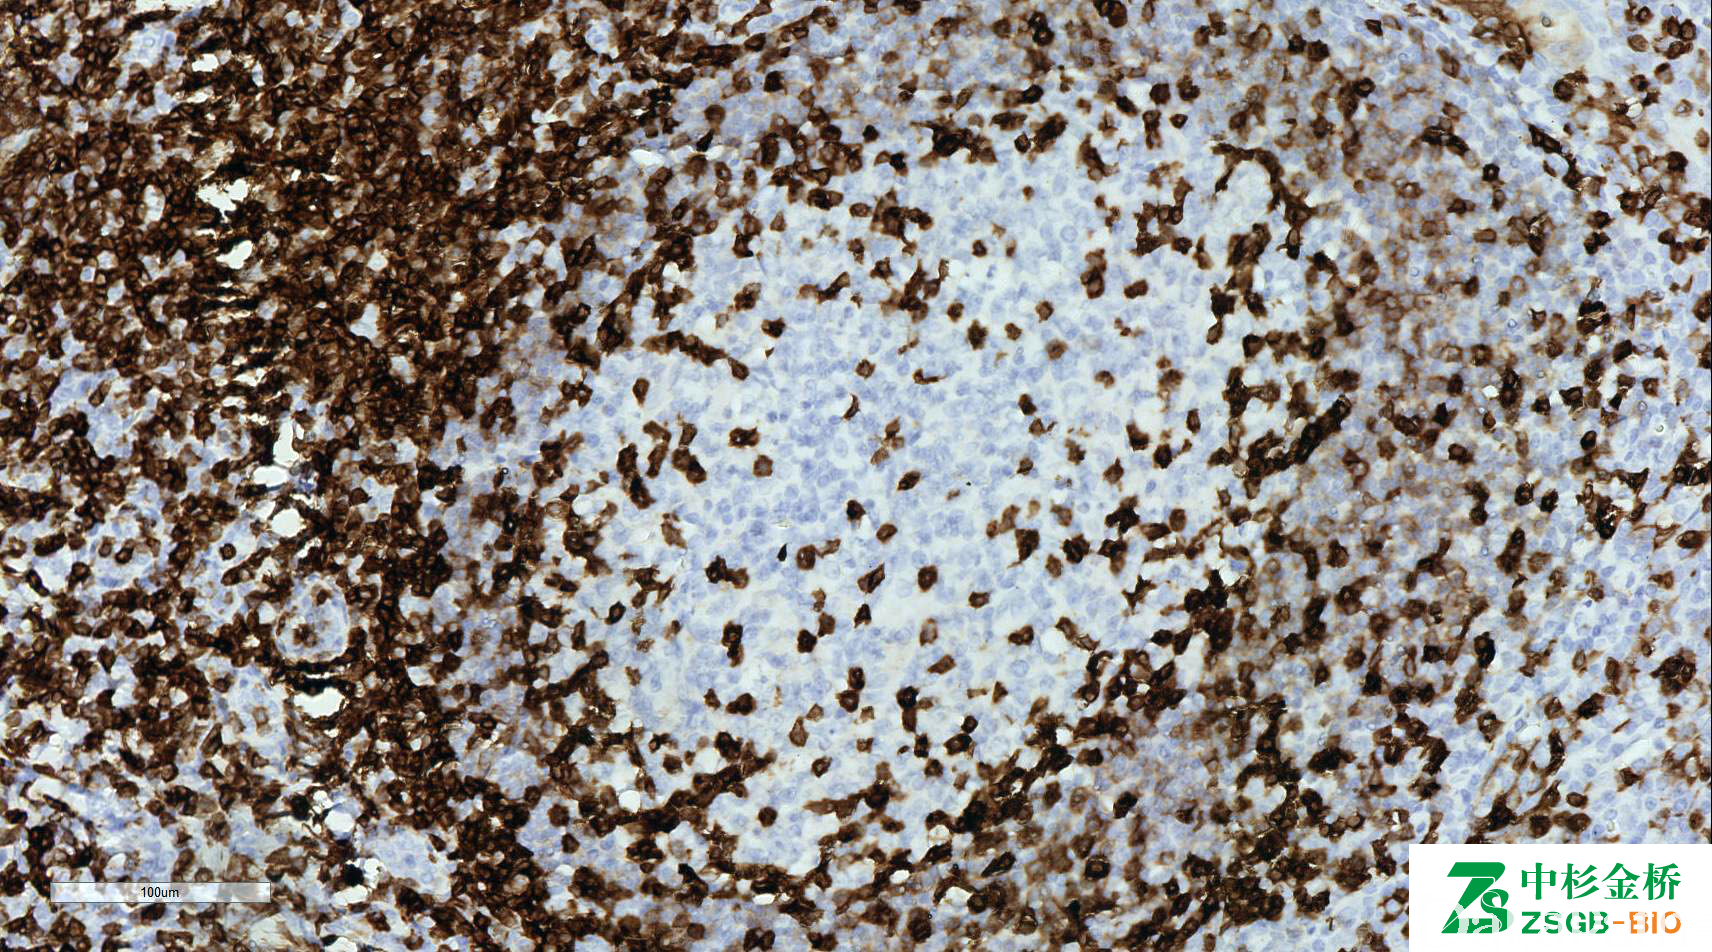

CD5

全 T 细胞标记,存在于人体 T 细胞表面的黏唐蛋白,少量正常 B 细胞及小 B 细胞淋巴瘤(CLL、MCL)阳性。

信号定位: 胞膜